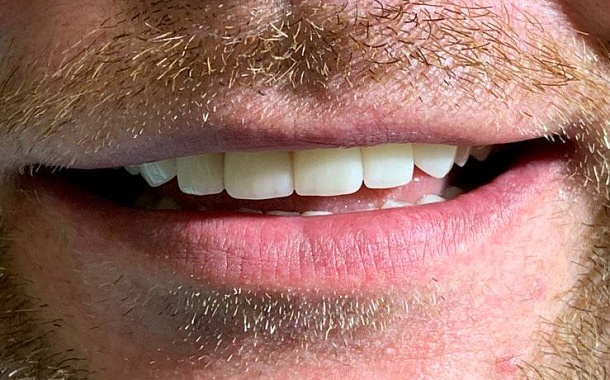

- Максимально точные и эстетичные ортопедические конструкции

- Долговечные результаты